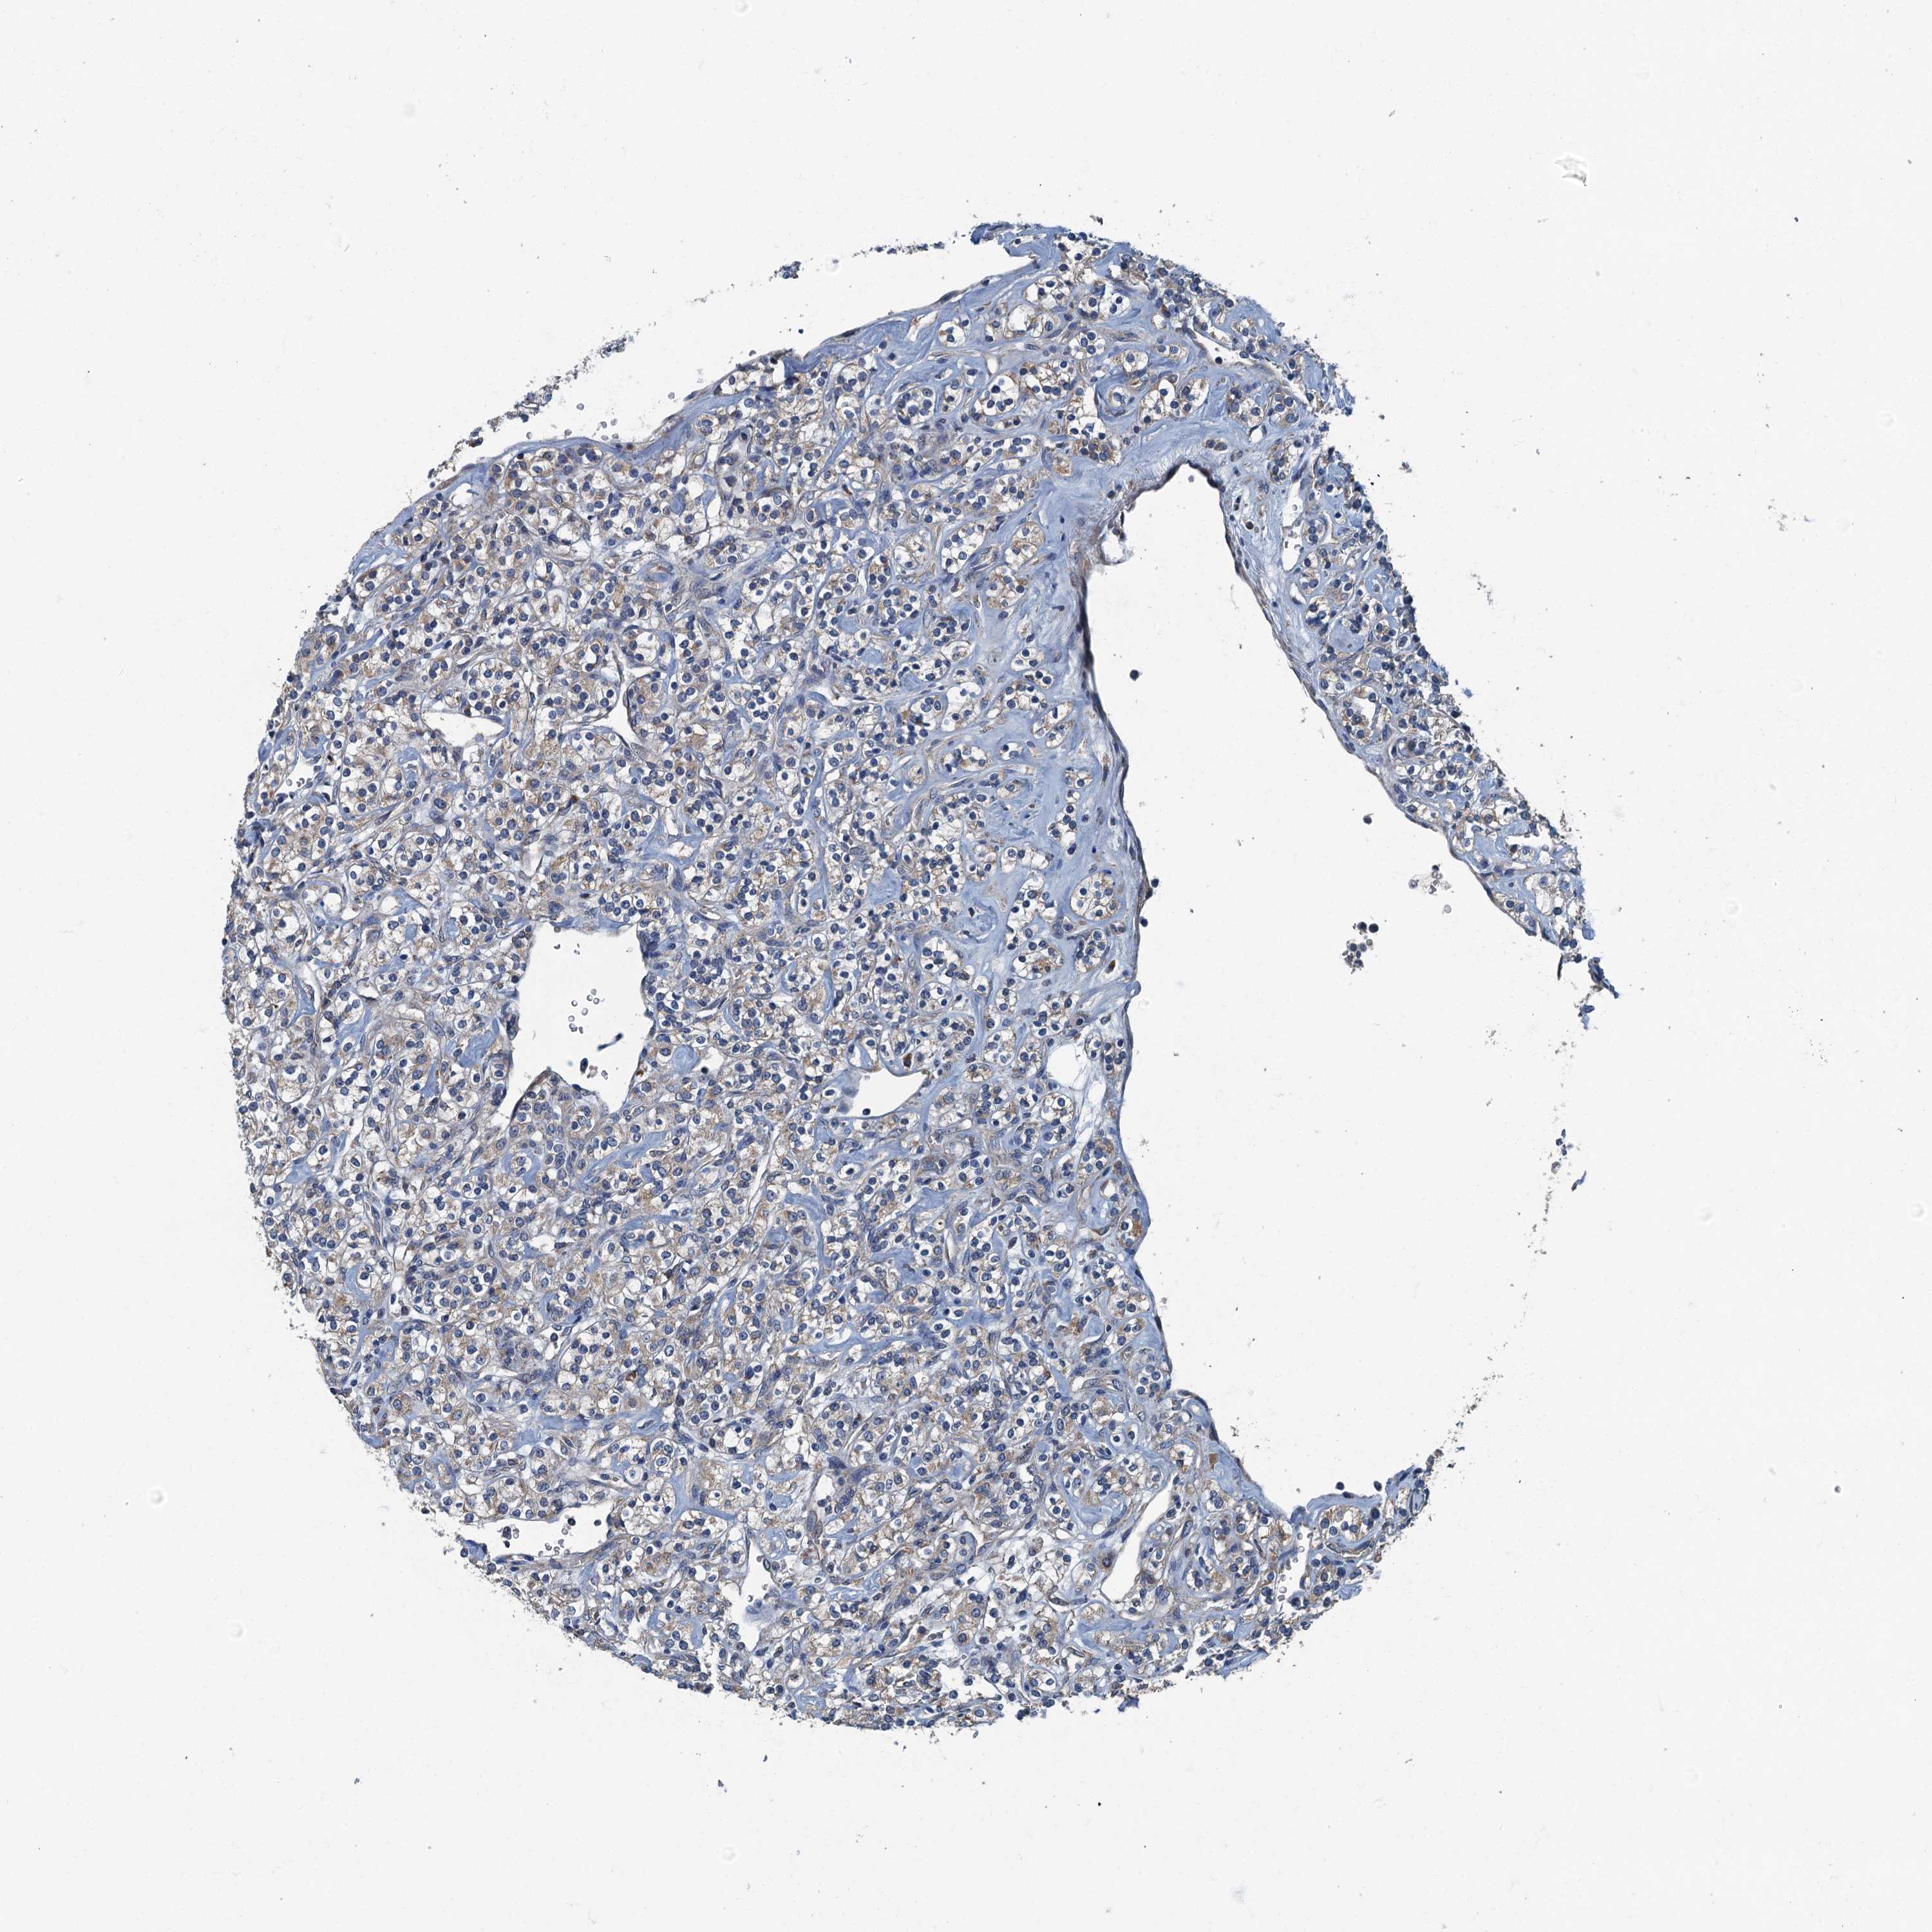

KIDNEY RENAL CLEAR CELL CARCINOMA (VALIDATION) - Interactive survival scatter ploti

The Survival Scatter plot shows the clinical status (i.e. dead or alive) for all individuals in the patient cohort, based on the same data that underlies the corresponding Kaplan-Meier plots. Patients that are alive at last time for follow-up are shown in blue and patients who have died during the study are shown in red.

The x-axis shows the expression levels (FPKM) of the investigated gene in the tumor tissue at the time of diagnosis. The y-axis shows the follow-up time after diagnosis (years). Both axes are complimented with kernel density curves demonstrating the data density over the axes. The top density plot shows the expression levels (FPKM) distribution among dead (red) and alive patients (blue). The right density plot shows the data density of the survived years of dead patients with high and low expression levels respectively, stratified using the cutoff indicated by the vertical dashed line through the Survival Scatter plot. This cutoff is automatically defined based on the FPKM cutoff that minimizes the p-score. The cutoff can be changed by dragging the vertical line or by entering a cutoff value in the square labeled "Current cut-off".

Under the Survival Scatter plot the p-score landscape (black curve; left axis) is shown together with dead median separation (red curve; right axis). Dead median separation is the difference in median mRNA expression between patients who have died with high and low expression, respectively. It is calculated as follows: median FPKM expression of dead patients with high expression - median FPKM expression of dead patients with low expression. This is intended to aid the user in visually exploring custom cutoffs and the associated p-scores and dead median separation.

Individual patient data is displayed and can be filtered by clicking on one or more of the category buttons on the top of the page. Categories describing expression level and patient information include: high, low, alive, dead, female, male and tumor stages. The scale of the x-axis can be toggled between linear and log-scale by clicking on the "x log" button. Mouse-over function shows TCGA ID, patient information and mRNA expression (FPKM) for each patient.

& Survival analysisi

Kaplan-Meier plots summarize results from analysis of correlation between mRNA expression level and patient survival. Patients were divided based on level of expression into one of the two groups "low" (under cut off) or "high" (over cut off). X-axis shows time for survival (years) and y-axis shows the probability of survival, where 1.0 corresponds to 100 percent.

DDX49 is not prognostic in Kidney Renal Clear Cell Carcinoma (validation)

Best expression cut offi

: 32.08

Average pTPM 26.7

Number of samples 100